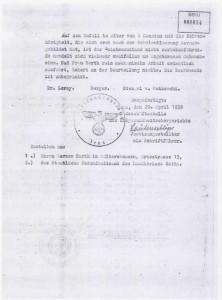

El 13 de abril de 1938 se revisó la apelación de Frieda Barth, una mujer de 38 años a la que las autoridades habían condenado a esterilización forzada. El tribunal rechazó su apelación e hizo efectiva la condena recalcando que Barth tenía "debilidad mental moderada congénita" y que su "habilidad mental estaba por debajo de la de un niño de 10 años". Entre las cuatro firmas que ratifican el fallo está la de Berger. / Archivos de la Stasi/Sage